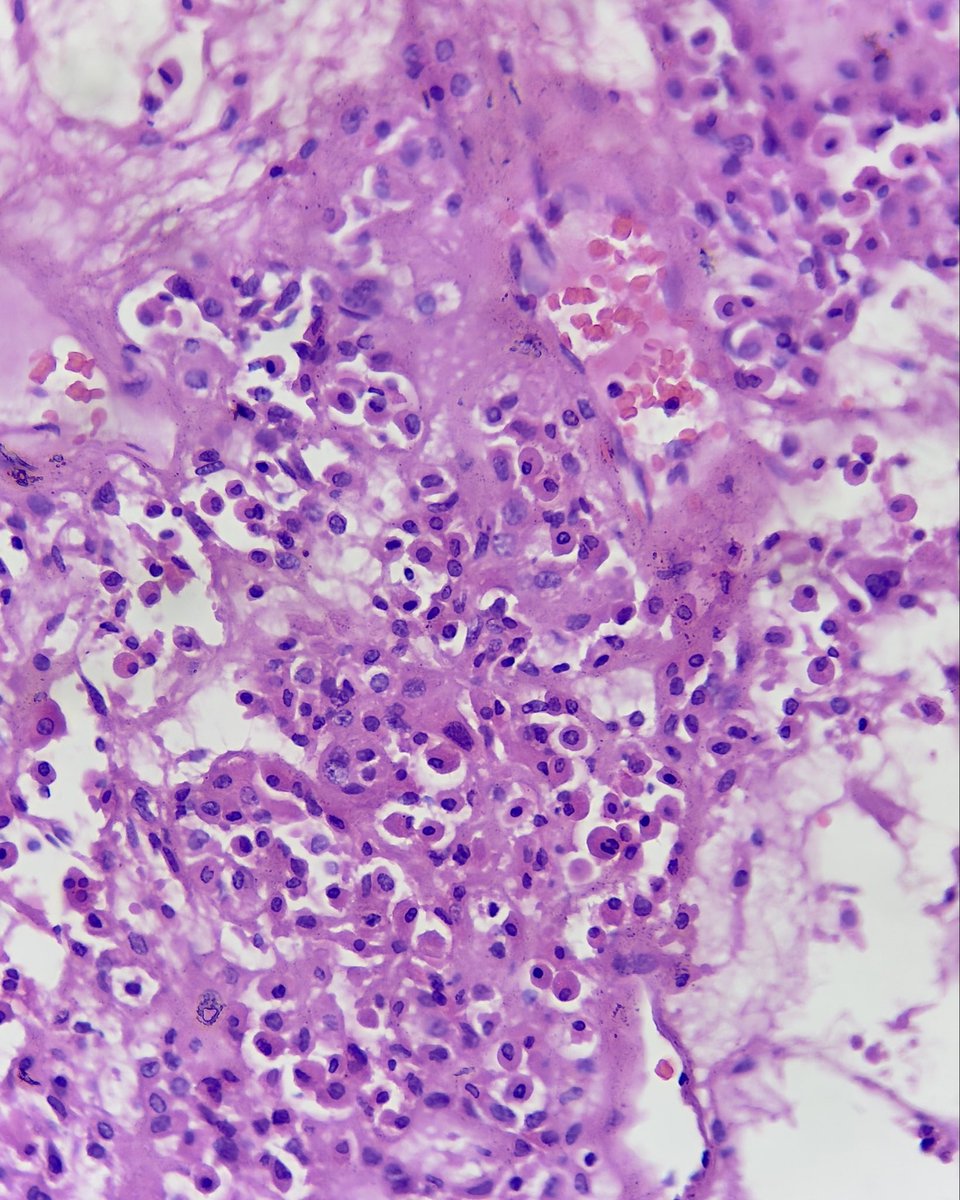

interesting #endopath/#GUpath adrenal🔬: pheochromocytoma with brown fat in surrounding adipose tissue @AMubeen_Path @DrCristinaMagi had a nice @TheUSCAP abstract on this topic a few years back

pheochromocytoma with brown fat in surrounding adipose tissue

@AMubeen_Path @DrCristinaMagi had a nice @TheUSCAP abstract on this topic a few years back